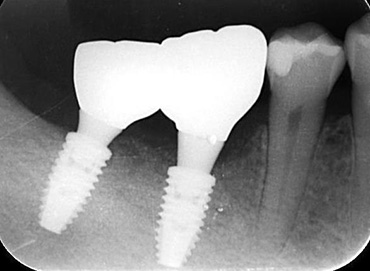

右下奥歯にインプラント治療希望にて来院された患者さん。欠損部の骨が大きく喪失しておりこのままでは適切な位置にインプラントを入れることができません。

|

インプラント埋入手術と同時に骨造成および結合組織の移植を行いました。

硬組織を造成することで理想的な位置にインプラントのポジショニングを行うことができました。

|

軟組織を増大することでインプラント周囲組織が長期に安定させることが可能になります。